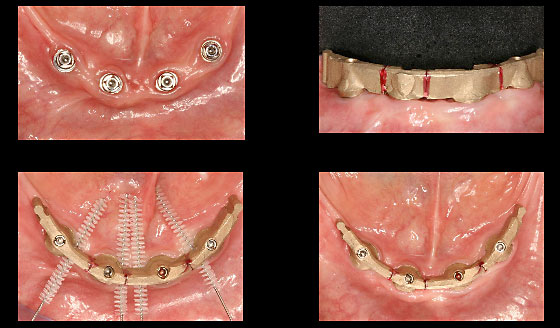

Fall: Implantatgetragene Stegarbeit bei zahnlosem Unterkiefer

Implantate Unterkiefer und vorbereiteter Abdrucklöffel

Abdrucknahme mit Positionskappen Implantate

Schematische Darstellung der Implantat- und Stegelemente

Anprobe des Stegs

OPG Steganprobe

Steganprobe

Ausgearbeiteter Steg und Anpassung der Unterkieferprothese

Eingegliederter Steg

Verlauf der Implantateinheilung bis Eingliederung Steg

Schlussbild - Implantatgetragene Unterkieferprothese